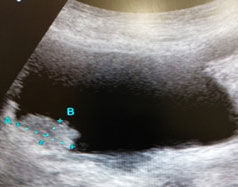

大変申し訳ありませんが例を上げるために画像を供覧致します。

画像1は膀胱内部に突出して膀胱腫瘍であり黒い部分が溜まった尿です。黒い部分が少ないと膀胱の壁が分厚くなる事で発見出来ない可能性が高くなります。前立腺の評価も膀胱内の尿が溜まっている事で正確な前立腺の体積を評価する事が可能となります (画像1、2)。

画像2:前立腺肥大

腎臓については腎結石、腎腫瘍、カラードップラーによる血流の評価等を行います。